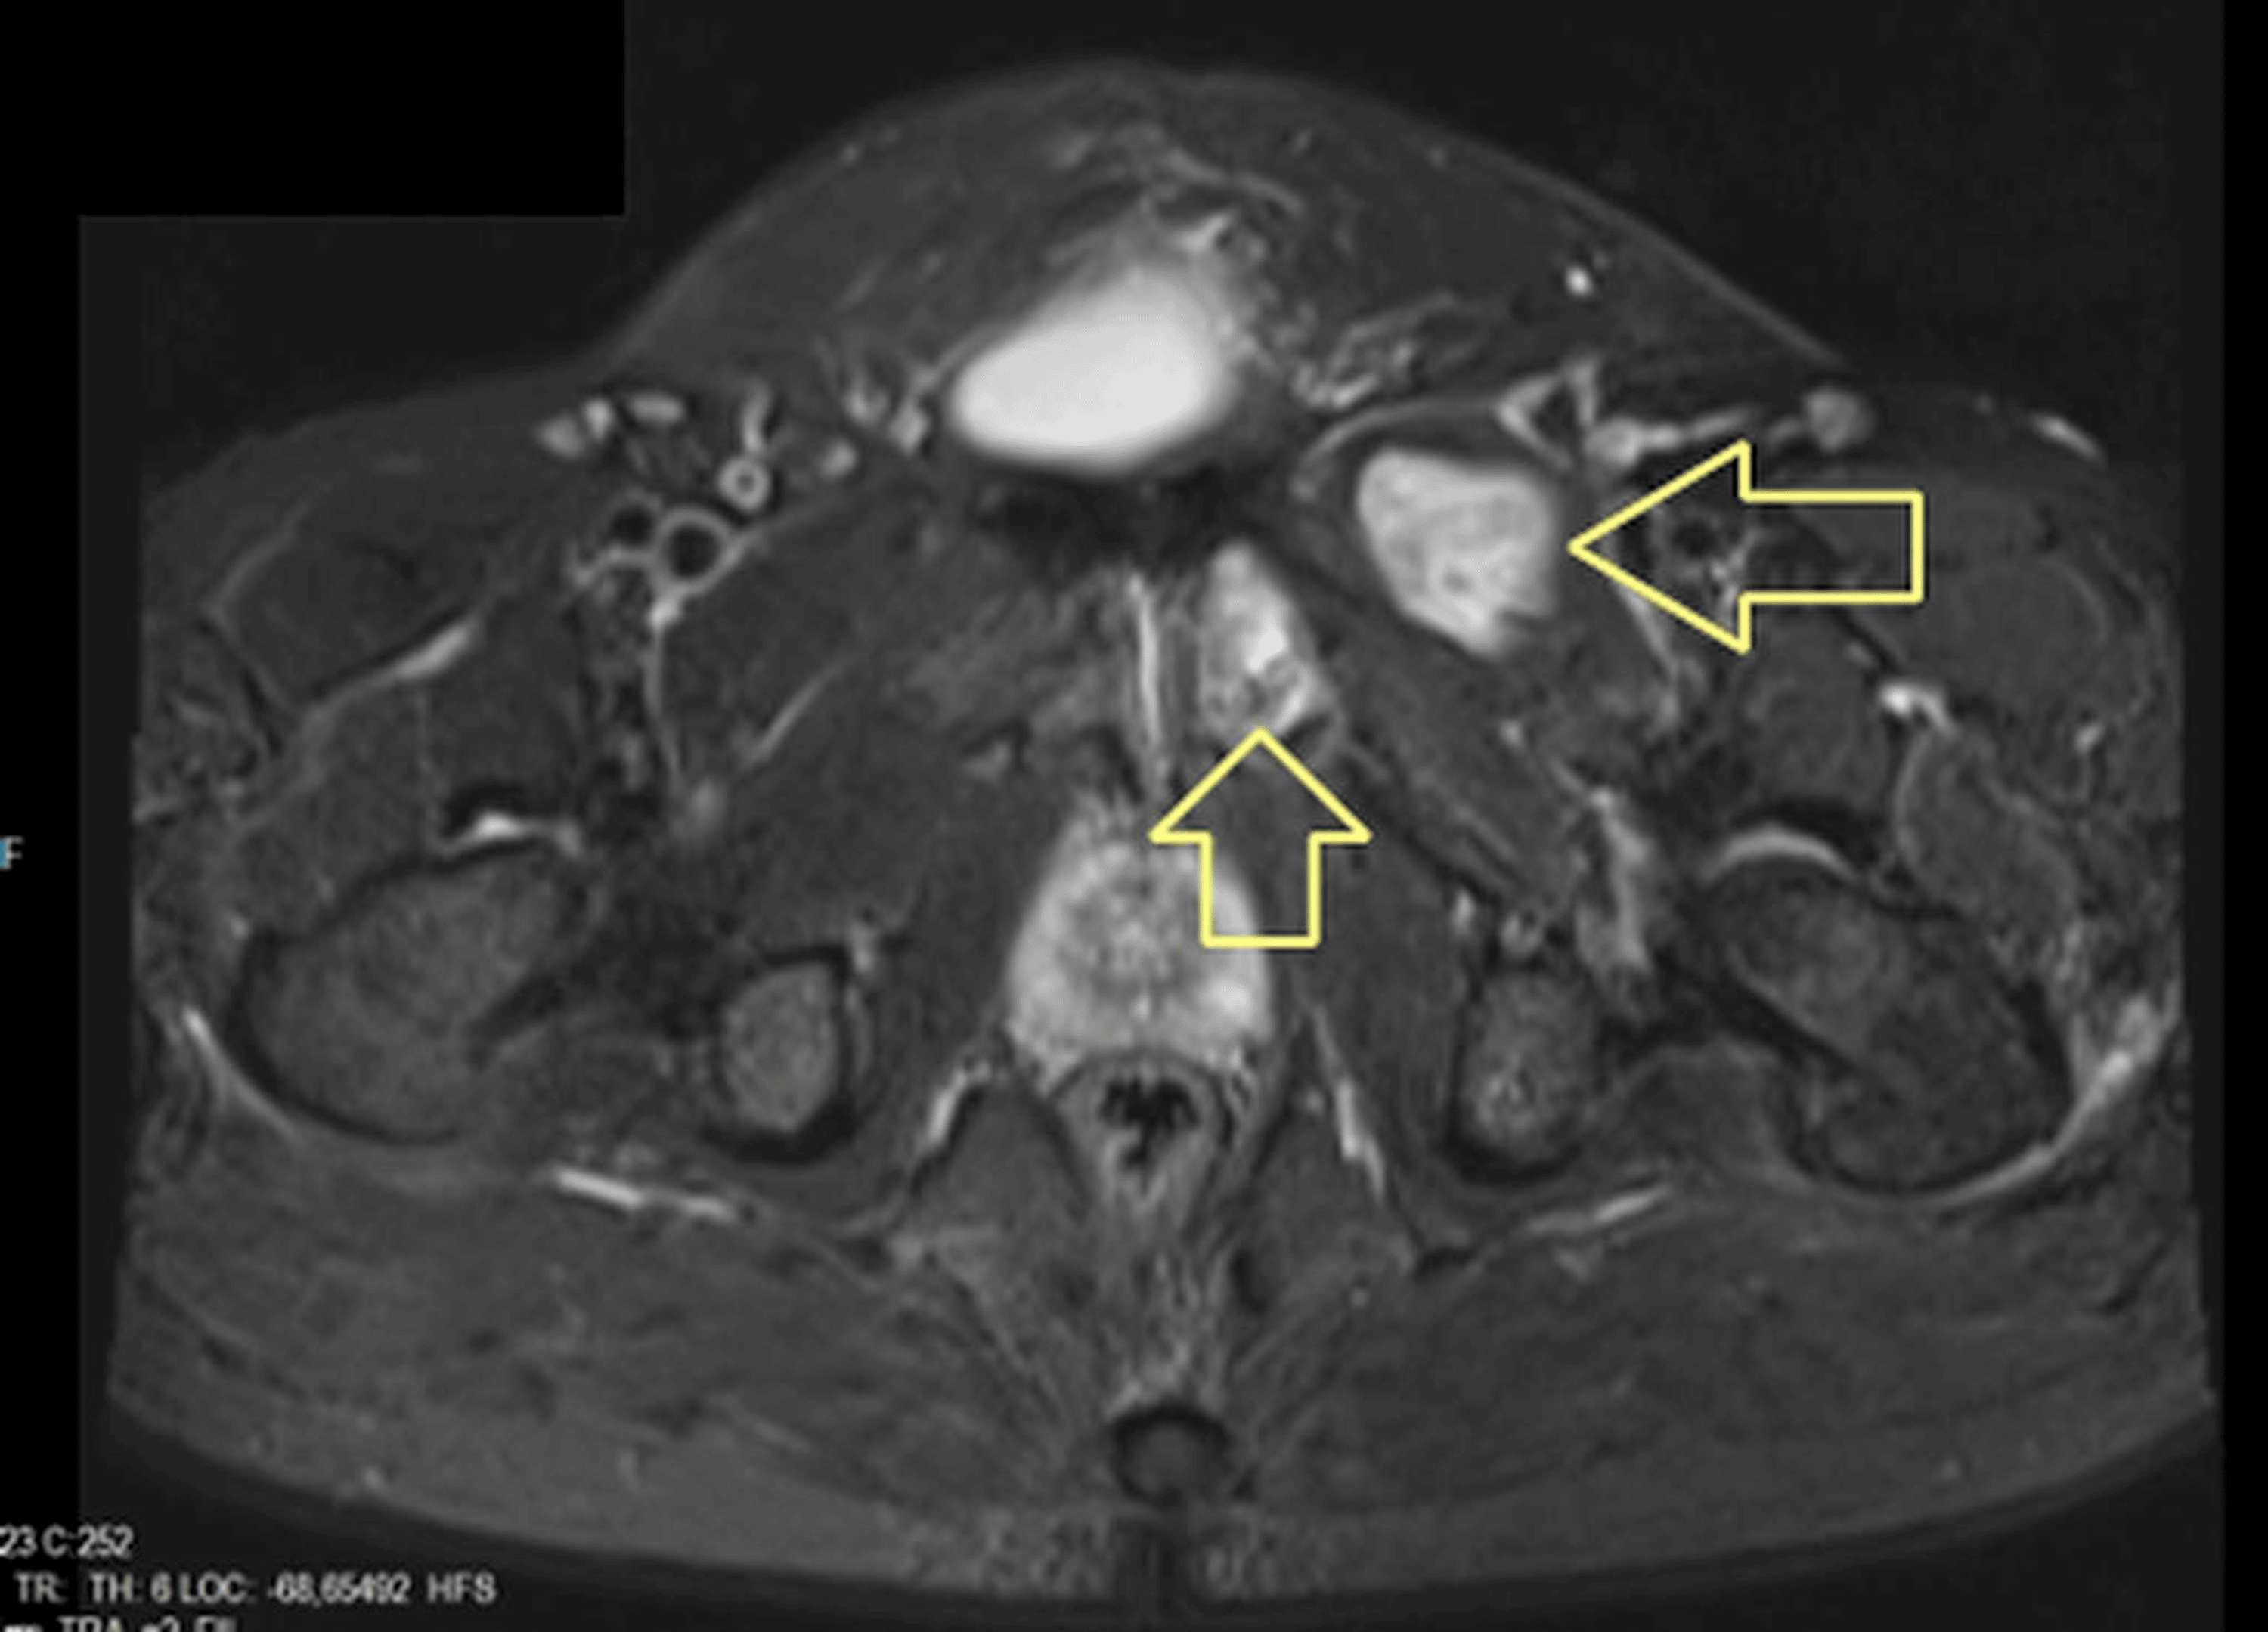

Cureus A Rare Presentation of Hydatid Cyst A Case Report of Localization in the Pectineus Muscle Cyst psoas syndrome is a rare form of muscle irritation that causes pain in your lower back, groin or butt. intramuscular myxomas are a rare benign type of soft tissue myxoma that is mesenchymal in origin. pectineus pain can be felt in your groin, inner thigh, or front top of your thigh. The pain can vary from a. Pectineus Muscle Cyst.